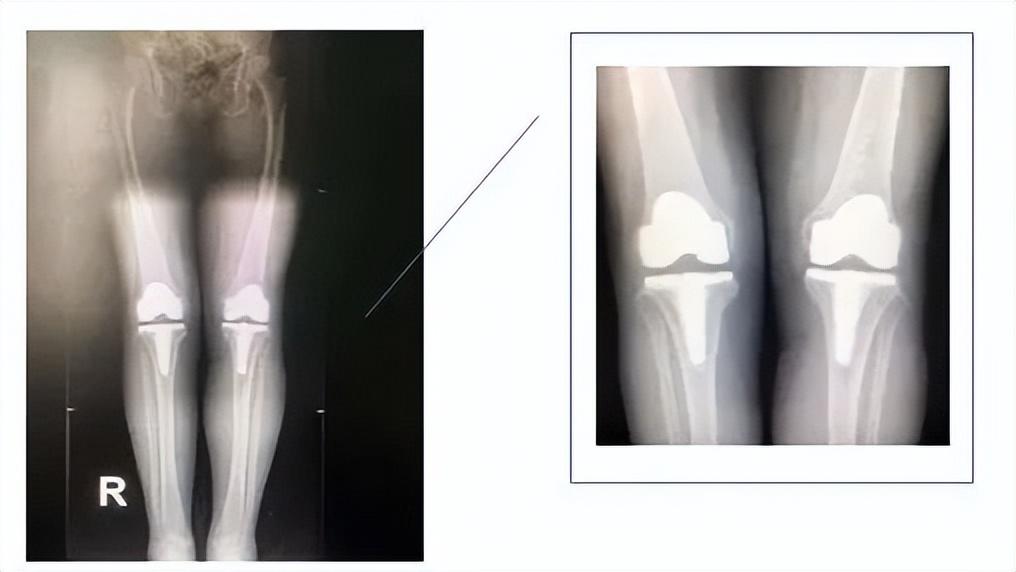

术前拍片示双膝内翻畸形、骨质增生

术后拍片示双膝关节立线纠正,内外间隙平衡